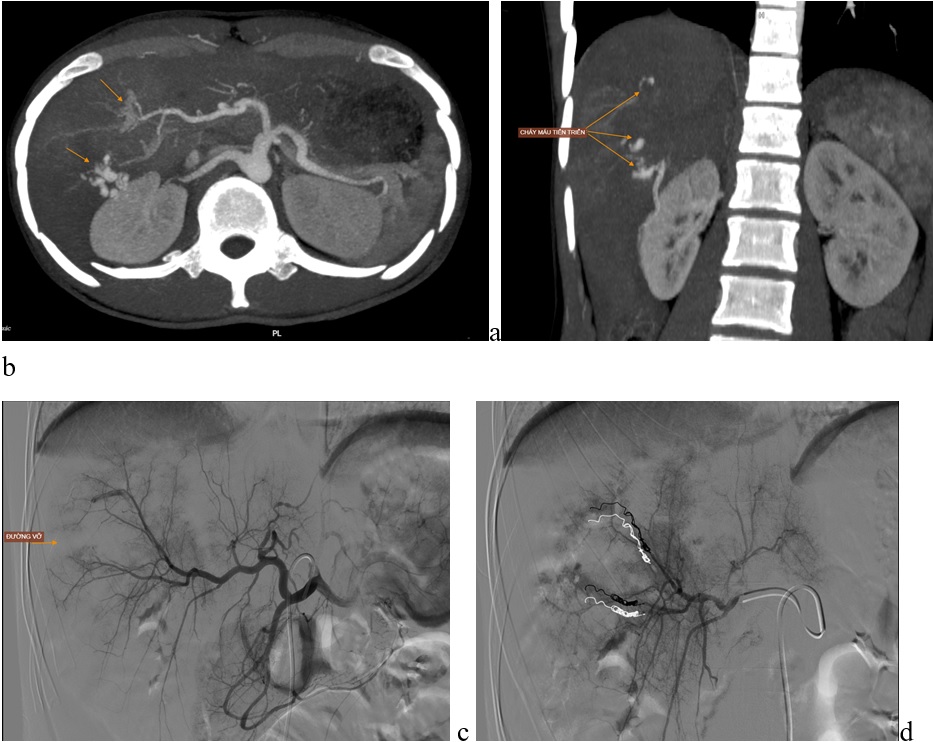

LIÊN TIẾP CÁC BỆNH NHÂN CHẤN THƯƠNG VỠ TẠNG ĐƯỢC ĐIỀU TRỊ ỔN ĐỊNH BẰNG PHƯƠNG PHÁP CAN THIỆP MẠCH

27/08/2024Chỉ tính riêng từ ngày 18/8 đến 22/8, Bệnh viện Đa khoa tỉnh Bắc Ninh tiếp nhận điều trị cấp cứu 04 bệnh nhân đa chấn thương, có vỡ tạng đặc gây chảy máu trong ổ bụng, được điều trị thành công bằng phương pháp can thiệp nội mạch.